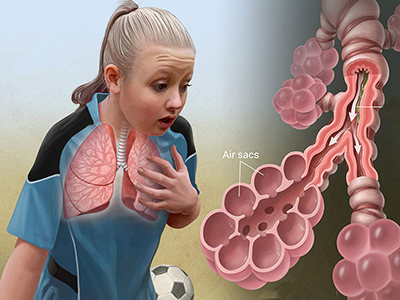

آسم یک مشکل طولانی مدت است که در مجاری تنفسی که هوا را به ریه ها می رسانند به وجود می آید و باعث ایجاد اشکال در تنفس می شود. بر اثر این بیماری مجاری تنفسی تنگ شده و هوا نمی تواند به راحتی به ریه ها برسد. آسم درمان قطعی ندارد اما اغلب بیماران می توانند با استفاده از برخی داروها و رعایت برخی نکات به راحتی آن را کنترل کنند.

علل حملات آسم

برخی از عوامل می توانند باعث بیشتر شدن التهاب در مجاری هوایی شده و آغازگر حملات آسم باشند. التهاب در مجاری تنفسی باعث تنگ تر شدن آنها می شود ودر عین حال ترشح خلط نیز افزایش می یابد و این عوامل باعث می شود ورود و خروج هوا به ریه ها بسیار سخت شده و تنفس به سختی انجام شود.

علائم آسم

تنفس کوتاه، نفس نفس زدن، احساس گرفتگی سینه، شنیدن صدای سوت هنگام تنفس و سرفه های پی در پی بدون قطع شدن از علائم حمله آسم هستند. حمله شدید آسم می تواند جان فرد بیمار را تهدید کرده و به خطر بیاندازد بنابراین باید سریعا به بیمار رسیدگی شود.